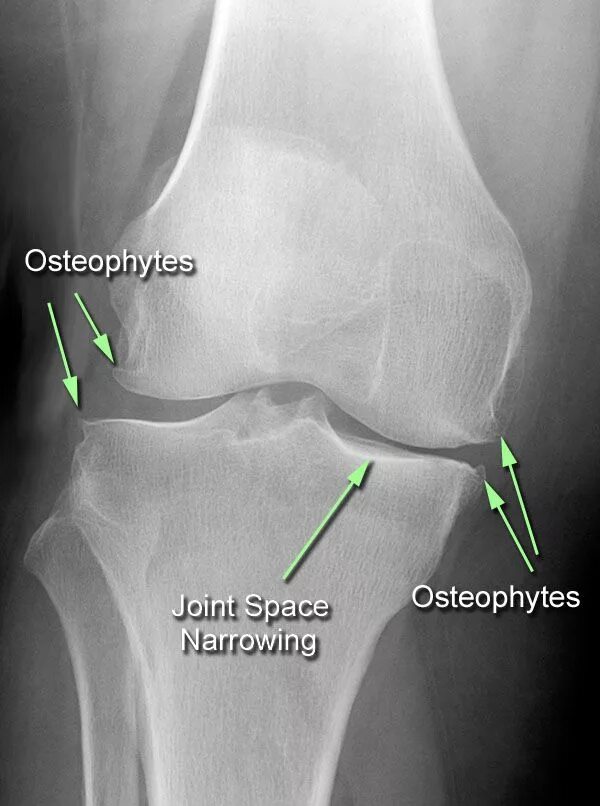

Что такое остеофиты коленного сустава как лечить